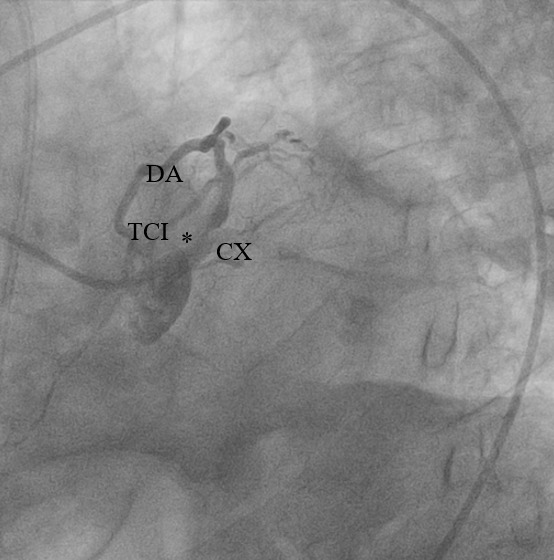

1. Arteria coronaria izquierda (Ver Figura 2)

- Tronco coronario izquierdo (TCI): se observó una lesión en bifurcación distal verdadera (Medina 1,1,1).

- Arteria descendente anterior (DA): se observó una lesión excéntrica calcificada crítica, con estenosis de 99% y flujo distal TIMI 2.

- Arteria circunfleja (CX): ocluída totalmente desde su ostium (flujo distal TIMI 0).